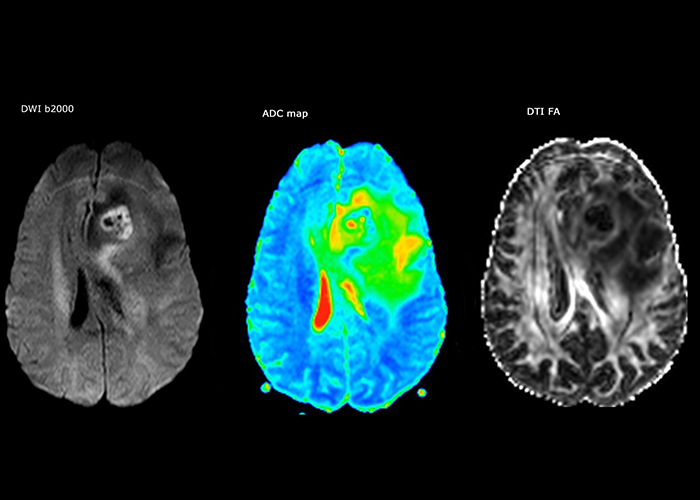

„Die größte Herausforderung besteht in der sachgemäßen Charakterisierung der Läsion und der angemessenen Information des Chirurgen, zum Beispiel was die Position der Gefäße und der funktionellen Bereiche betrifft. Gelegentlich ist eine sehr umfassende Untersuchung notwendig, beispielsweise wenn eine Raumforderung an einem anderen Krankenhaus festgestellt wurde und der Patient anschließend an uns überwiesen wurde. Wir führen dann eine Charakterisierung der Läsion und eine präoperative Bildgebung in einer Untersuchung durch, d.h. sowohl eine morphologische als auch eine funktionelle Beurteilung. Für die morphologische Beurteilung verwenden wir eine T1-gewichtete Prä- und Postkontrastbildgebung sowie FLAIR für die Beurteilung der Infiltration und Diffusion. Für die funktionelle Charakterisierung führen wir eine Perfusionsbildgebung, eine MR-Spektroskopie und eine suszeptibilitätsgewichtete Bildgebung durch, um Mikrogefäße oder Mikroblutungen innerhalb der Läsion aufzuspüren[4]. Für die präoperative Untersuchung führen wir eine spezifische morphologische Bildgebung durch, die mit dem Navigationssystem kompatibel ist. Je nach Position des Tumors erfolgt fMRT oder TDI.“